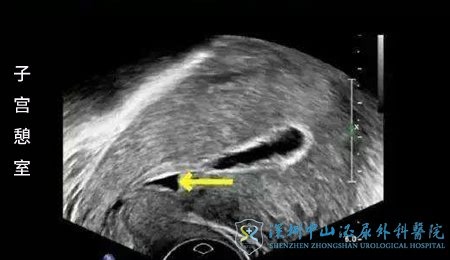

经过夫妻双方助孕前的一套检查发现,夫妻双方体检没有发现异常。但张女士剖宫产后疤痕切口修复差,形成了一个疤痕憩室。张女士也恍然大悟,难怪生完后每次来月经都滴滴答答不太干净。徐芬医生告诉张女士,月经拖尾难以干净就是疤痕憩室惹的祸。

2019年1月张女士成功获得10枚卵子,培养成3枚可用囊胚,但没有移植鲜胚。原因是促排卵期间发现了宫腔积液。徐芬医生告诉张女士:试管备孕期间,会有部分患者在B超时发现宫腔积液,这就好比田地出现积水,种子种进去会过度发胀,无法正常生根发芽一样,胚胎移植进去也无法正常着床。张女士的宫腔积液与疤痕憩室相关,不排除合并子宫内膜炎可能,这些亚临床的宫腔感染损伤子宫内膜,同时使周围组织释放细胞因子、前列腺素等,导致宫腔渗出增多出现宫腔积液。